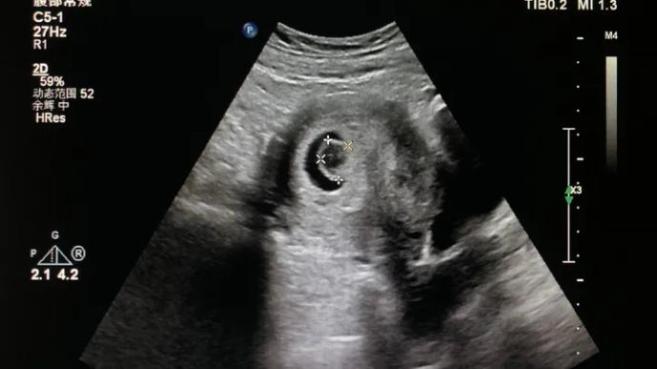

空孕囊的诊断

空孕囊的诊断主要依靠超声检查。一般来说,在怀孕5周左右通过阴道超声即可看到孕囊,到了6-7周应能观察到胚胎和胎心。

如果超声检查显示孕囊内无胚胎或胎心跳动,可能会诊断为空孕囊。但为了确诊,医生通常会建议隔一段时间再次进行超声检查以排除检查时机不当等因素。